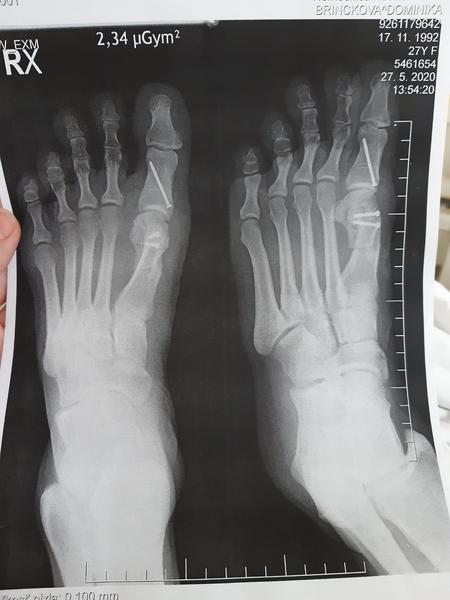

Operácia haluxov

@svetluska211 vlastne to je ta metoda scarf

@dominiqwa Ja mám pravú nohu takto robenú. Skoré uzdravenie prajem.